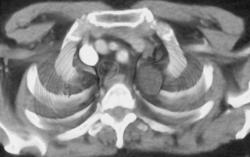

Scaphoid Fracture